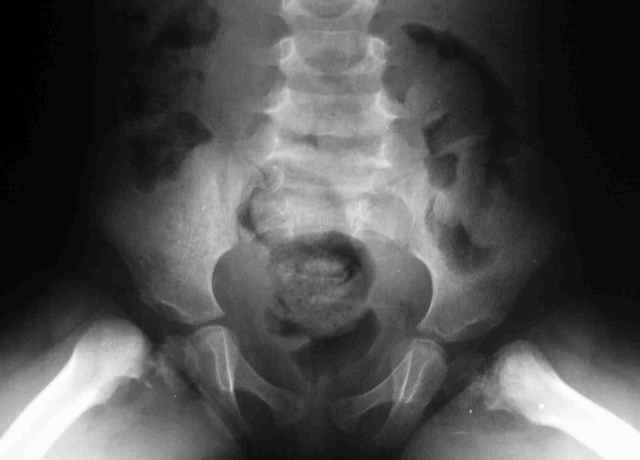

Дорогие коллеги,Нужен совет.Девочка 3 лет -врожденная двусторонняя кокса вара и как водится ограничено отведение и ротационные движения и *матросская* походка в развалочку.

У Вашей пациентки Двухсторонний Врождённый Дефект Проксимального Бедра сопровождающийся Двухсторонней Ацетабулярной Дисплазией.

Спасибо за комментарии, Врожденная кокса вара может рассматриваться как вариант фокального дефицита проксимального отдела бедра, но как-то не складывается у меня впечатление о дисплазии впадин и дефекте проксимального бедра - сформирована вертельная область, хотя шейка бедра практически не видна,коэффициент покрытия проксимального эпифиза нормален. Что обращает на себя внимание - это расширенные и вертикально ориентированные зоны роста( угол Хильгенрейнера около 90 градусов и формирование остеофита по нижнему контуру ростковой зоны.